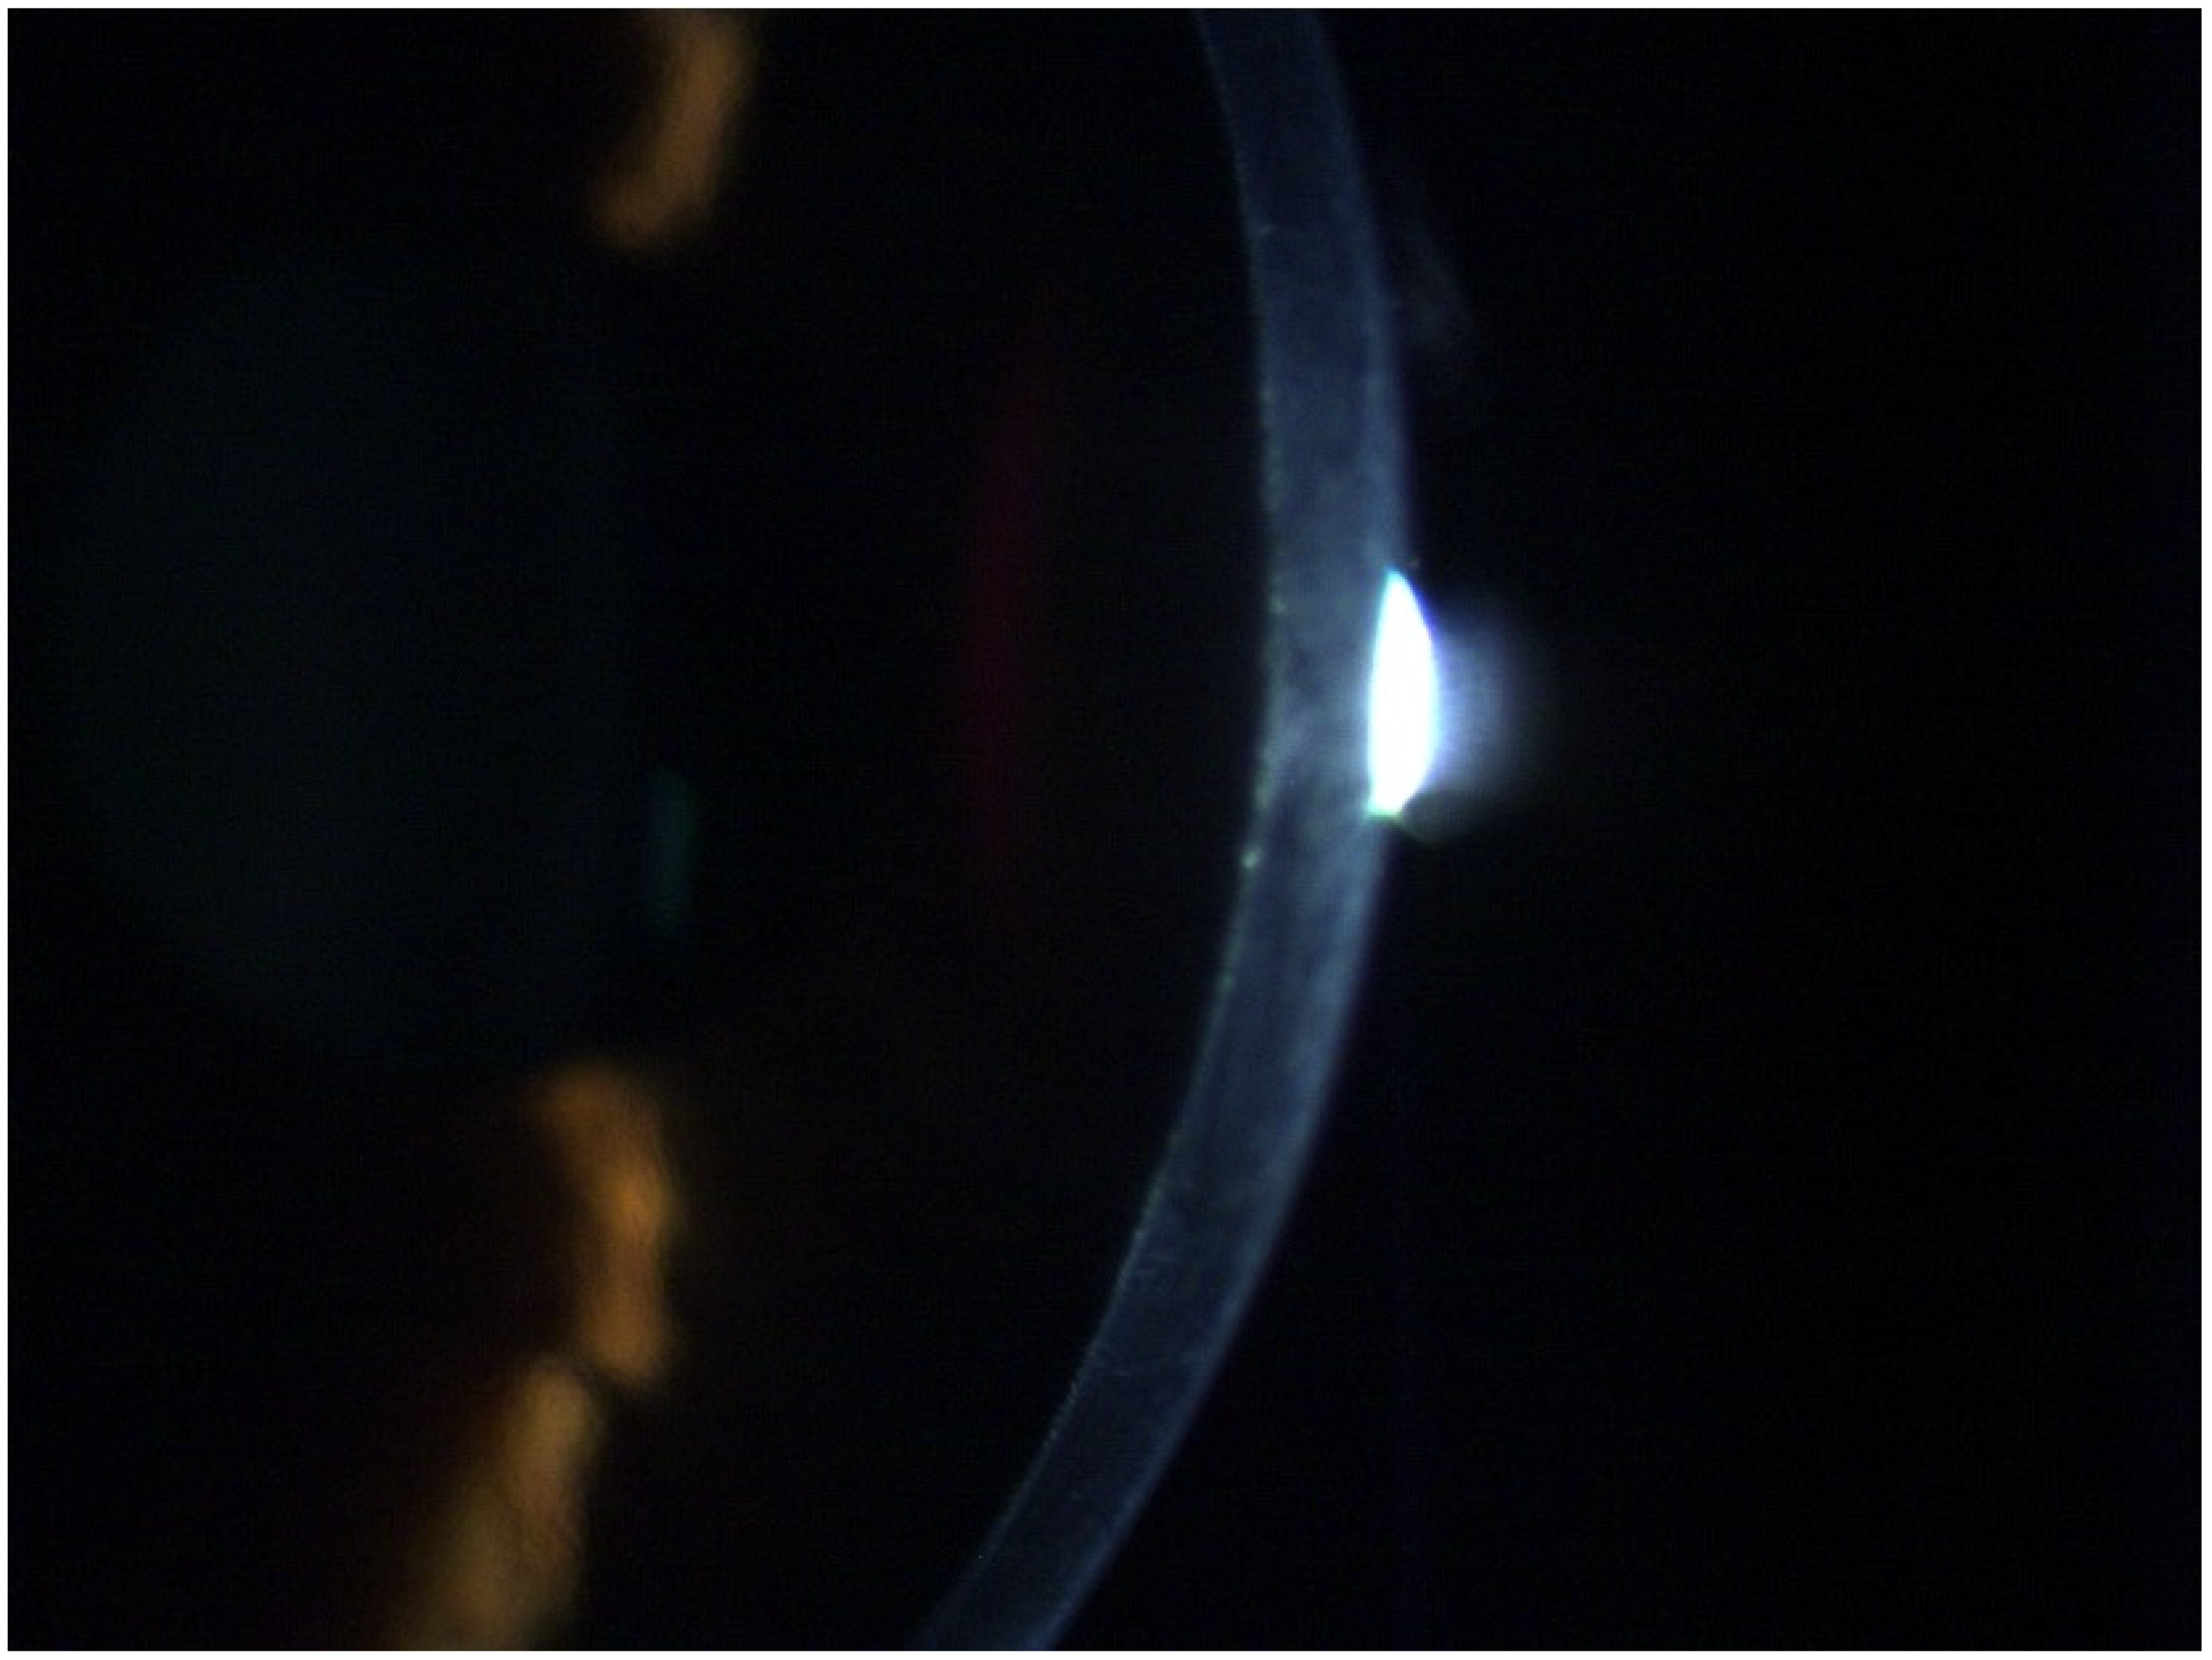

Combined Rotating Ultra-High-Resolution Spectral Domain OCT and Scheimpflug Imaging for In Vivo Corneal Optical Biopsy

1.3. The Pentacam® Cornea OCT

2. Materials and Methods

3. Results